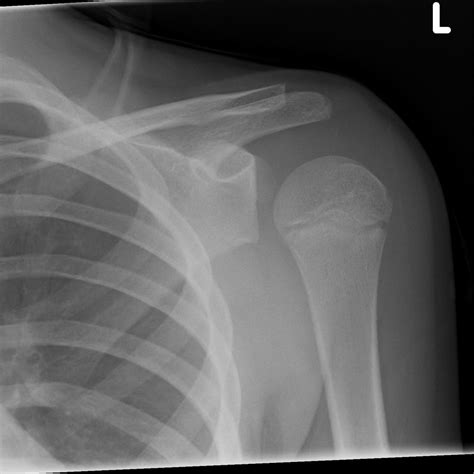

Posterior shoulder dislocations | The BMJ

1800×1218

• Imaging Tests: X-rays are the primary imaging tool used to confirm the diagnosis. Additional tests such as CT scans or MRIs may be ordered to evaluate the extent of the injury and any associated damage to surrounding tissues.